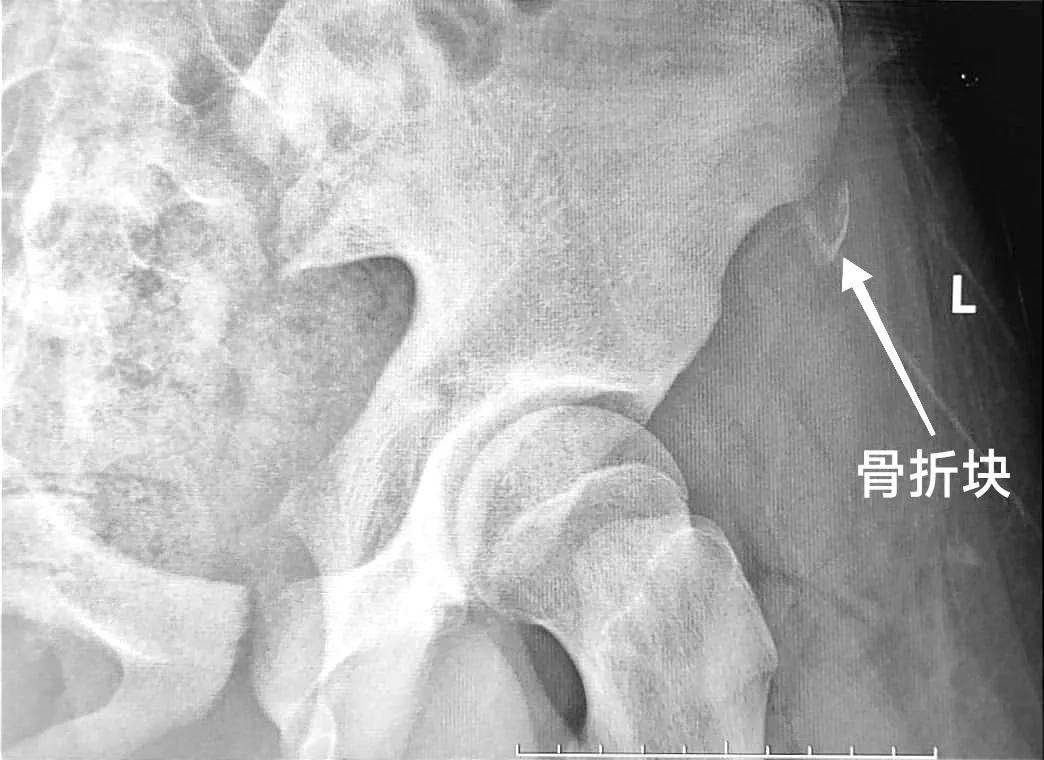

拍片一看,是“髂前上棘撕脱性骨折”。

髂前上棘撕脱性骨折多好发于青少年,这个部位有个骨骺线,是生长发育中骨头生长的部位,比较薄弱。

当参加剧烈运动时,骨面上附着的缝匠肌突然收缩、牵拉,就容易把止点处的骨块拉下来,比如踢足球、跳远、跳高、短跑、冲刺跑、打篮球这些运动过程中,突然摆动大腿使其伸直或髋部屈曲,加之收腹的动作,这时候会使缝匠肌张力突然增加或者缝匠肌突然的收缩,导致髂前上棘撕脱骨折。当发生骨折时运动员会突然感觉髂前上棘处疼痛、肿胀,大腿不敢活动,这时候要注意可能发生骨折,要及时就医。